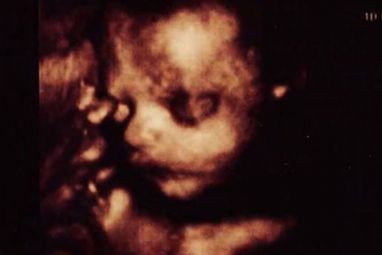

Podaci dobiveni ultrazvučnim pregledom pretvoreni su u frekvencije, frekvencije u tonove i na taj način dobivena je jedinstvena melodija bebe.